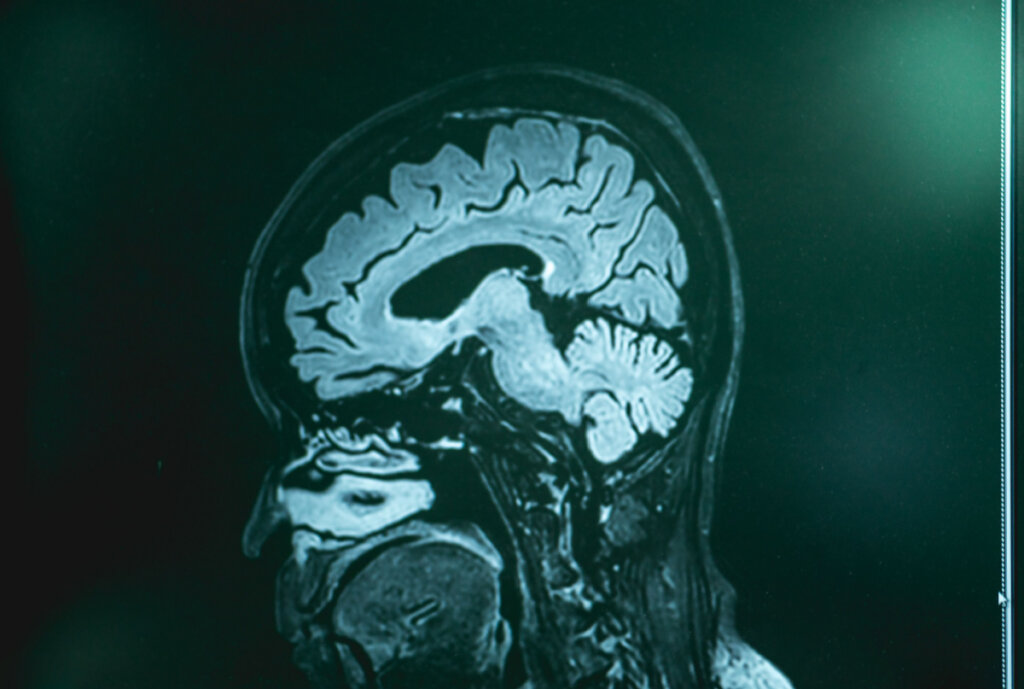

Trotz des derzeitigen Mangels an Wissen über die Ursache dieser besonderen Art von Demenz gibt es verschiedene Hypothesen. Mithilfe von bildgebenden Verfahren kann bei den Patienten eine Atrophie, also ein “Schrumpfen” bestimmter Bereiche der Hirnrinde, insbesondere im temporalen und frontalen Kortex, beobachtet werden.